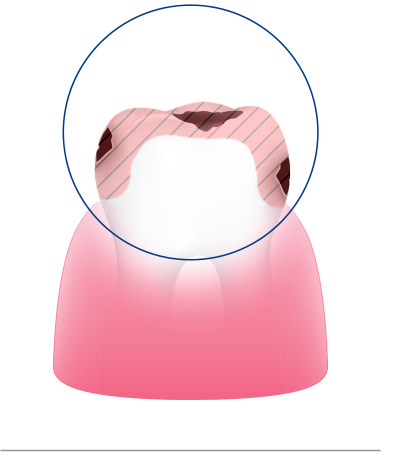

치아

연세일등치과는 충치를 단순히 메우는 것보다

치아의 남은 구조를 얼마나 많이 보존할 수 있을지를

먼저 생각합니다.

이를 위해 치료 전 단계부터 정밀한 진단을 통해

건강한 부위와 손상된 부위를 구분하고,

치료 범위를 필요한 만큼만 설정합니다.

이러한 보존 중심 접근은 단순한 철학이 아니라,

연세일등치과의 진료 시스템 그 자체입니다.